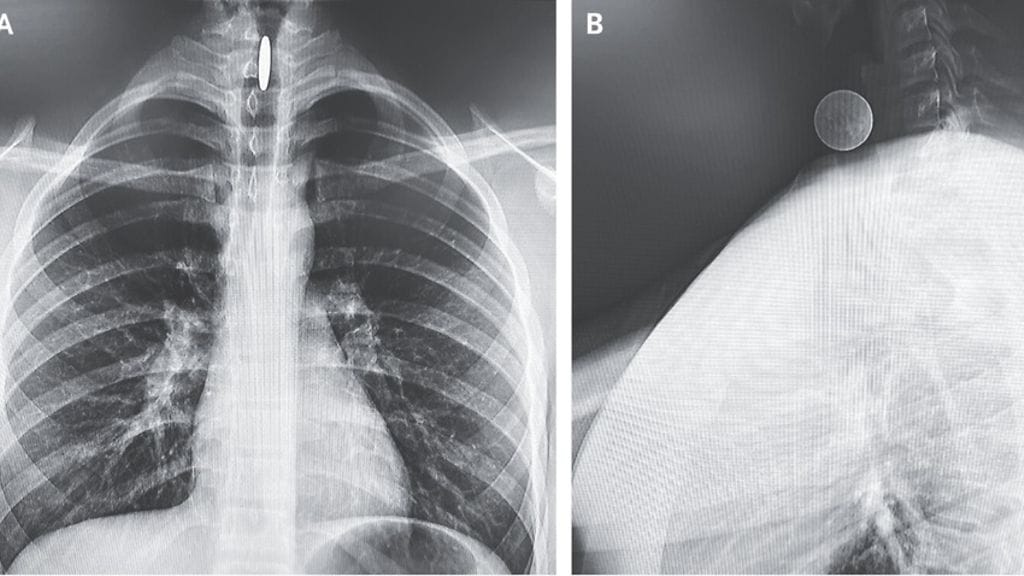

14-vuotias poika joutui ensiapuun sen jälkeen, kun hän nieli vahingossa neljännesdollarin kolikon. Se jäi hänen hengitysteihinsä.

Neljännesdollarin kolikon halkaisija on 24,26 millimetriä ja paksuus 1,75 millimetriä.

New England Journal of Medicine -lehdessä julkaistun tapausraportin mukaan perusterve 14-vuotias meni ensiapuun valittaen "käheydestä ja nielemisvaikeuksista" kuusi tuntia sen jälkeen, kun oli vahingossa nielaissut neljännesdollarin.

– Vahingossa niellyt vierasesineet kulkeutuvat yleensä ruokatorveen, tapausraportissa kerrotaan.

Raportissa kerrotaan, että isompien lasten tapauksessa ne päätyvät yleensä henkitorveen tai keuhkoputkeen, ei kurkkuun, kuten tässä tapauksessa. Syynä on painovoima ja hengitysteiden suurempi koko.